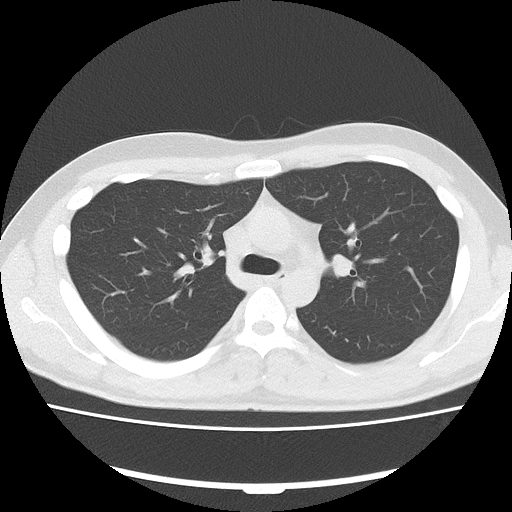

胸部のCT 胸部CT検査 | 呼吸器の検査 | 各検査を知る | 人間ドック | 健診の詳細情報

胸部CT検査 | 呼吸器の検査 | 各検査を知る | 人間ドック | 健診。CT装置のご紹介 | こうのす共生病院|埼玉県鴻巣市。胸部CT | 画像診断検査 | 各検査を知る | 人間ドック | 健診会。医師解説】胸部CT検査の基本とCT写真の見方完全ガイド(※言い。「胸部のCT」村田 喜代史 / 上甲 剛 / 村山 貞之定価: ¥ 15000#村田喜代史 #村田_喜代史 #上甲剛 #上甲_剛 #村山貞之 #村山_貞之 #本 #自然/医療・薬学・健康裁断済み中身は未使用に近い